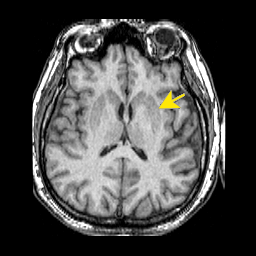

078striatumPutamen.png